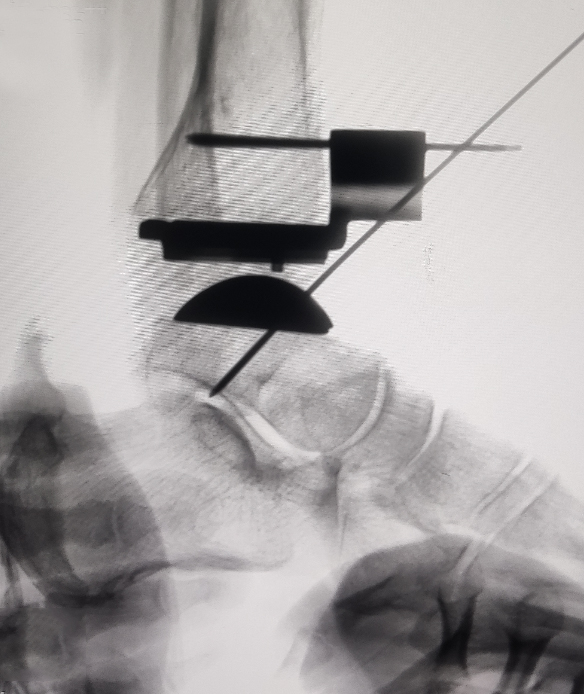

在为贾女士进行综合评估后,手足外科吕振刚副主任医师团队决定为她实施右踝关节置换术。手术由吕振刚主刀,桂琦副主任医师、赵英伦主治医师协作完成。术中,术者精准截骨,最大程度恢复关节力线;结合术中影像,确保假体定位精准;选择合适假体系统,增强了术后的稳定性与耐久性。

手术顺利完成,贾女士术中生命体征平稳,无并发症,踝关节疼痛症状明显缓解,并于近日顺利出院。